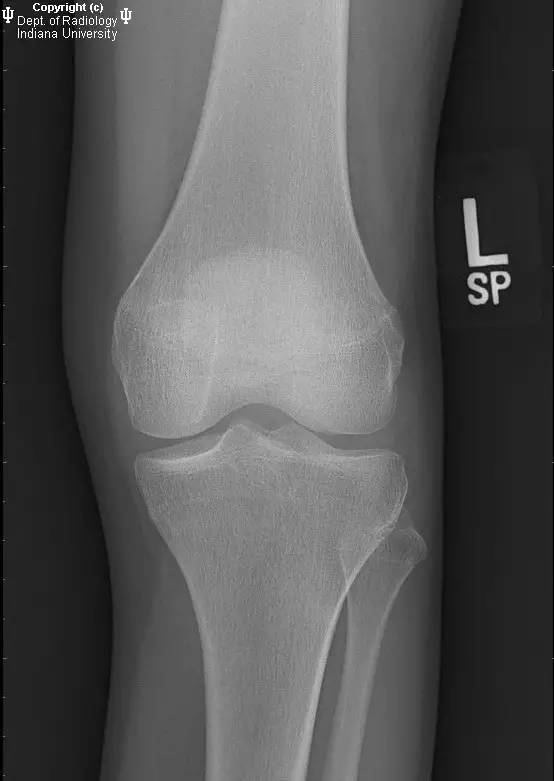

- 膝关节X线:无急性骨折、脱位或半脱位。关节间隙良好。无关节积液。

【诊断】缺血性坏死(AVN)及骨梗死

AVN and bone infarcts

- X片骨梗死示松质骨内不规则或匐行性边界的病变。AVN表现为弧形软骨下透亮区,周围可见斑片状骨丢失区。